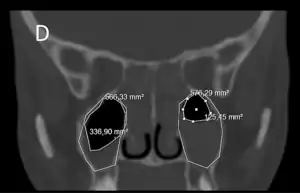

En casos con sospecha de complicaciones, que son excepcionales, se pueden realizar exámenes vídeo-endoscópicos, así como un TAC (tomografía axial computarizada). Hay que destacar que la utilización exclusiva de los rayos X para el diagnóstico de las sinusopatías está desaconsejada, debido a la alta tasa de fallos que este examen presenta para los senos faciales, incluyendo falsos positivos.